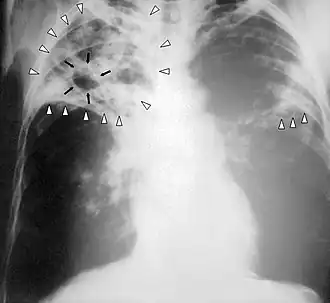

Diagnostic radiologique

La modalité de diagnostic radiologique se révèle très utile et indiquée comme étant un examen de première intention en cas de tuberculose pulmonaire et ostéoarticulaire[78]. Cela est justifié par les images radiologiques plus ou moins spécifiques à la tuberculose. La littérature rapporte que la spécificité varie de 27 à 81 % selon l’étude. Les imageries idéales et révélatrices de la tuberculose répondent à certains attributs dont le premier est lié au siège. En raison de l’affinité que les BK ont envers les régions aérées, la lésion radiologique est souvent observée dans les parties hautes des poumons. Néanmoins, l’image radiographique peut contenir différentes formes :

- infiltrat : traduisant des lésions débutantes de l’infection via une opacité peu dense, hétérogène et étendue ;

- nodule : granulome de taille variable, isolé ou groupé ;

- tuberculome : nodule isolé pseudotumoral ;

- caverne : excavation par perte de substance au sein d’un infiltrat, aux parois épaisses.

Les cavernes sont une complication fréquente de la tuberculose pulmonaire[55]. On appelle caverne une cavité creusée au sein du parenchyme pulmonaire[56]. Les bacilles tuberculeux se développent initialement dans le poumon sous forme de nodules, appelés granulomes, qui sont peu à peu entourés de lymphocytes et de macrophages destinés à contenir l'infection[55]. Un granulome peut évoluer soit vers la disparition sans cicatrice, soit vers la caverne, sans que les mécanismes sous-jacents soient compris en totalité[56]. Les vestiges de macrophages détruits occupent le centre du granulome et forment la majeure partie de la nécrose caséeuse[56]. Chez certains patients, cette nécrose caséeuse se liquéfie et devient un milieu de culture adapté aux bacilles, qui prolifèrent. Des enzymes protéolytiques érodent alors la capsule fibreuse située en périphérie du granulome, et son centre liquide peut alors se vider peu à peu[56]. Lorsqu'une caverne tuberculeuse arrive en communication avec l'arbre bronchique, la dissémination des bacilles dans l'air expiré augmente la contagiosité[55],[57]. Par ailleurs, la quantité importante de bacilles contenus dans les cavernes favorise le développement de résistances aux anti-tuberculeux[57].